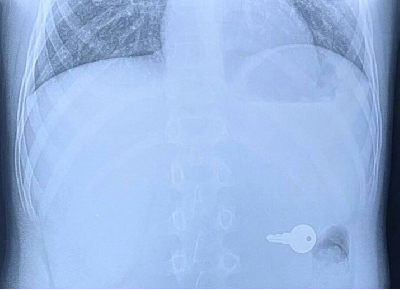

В Городецкой ЦРБ во время рентгена в теле пациента увидели ключ. Об этом рассказал сотрудник ННГУ Алексей Никонов в своем телеграм-канале «Бокал прессека».

Алексей Никонов опубликовал фотографию рентгена, где видно тело человека, а с левой стороны ниже сердца заметно четкое очертание небольшого ключа.